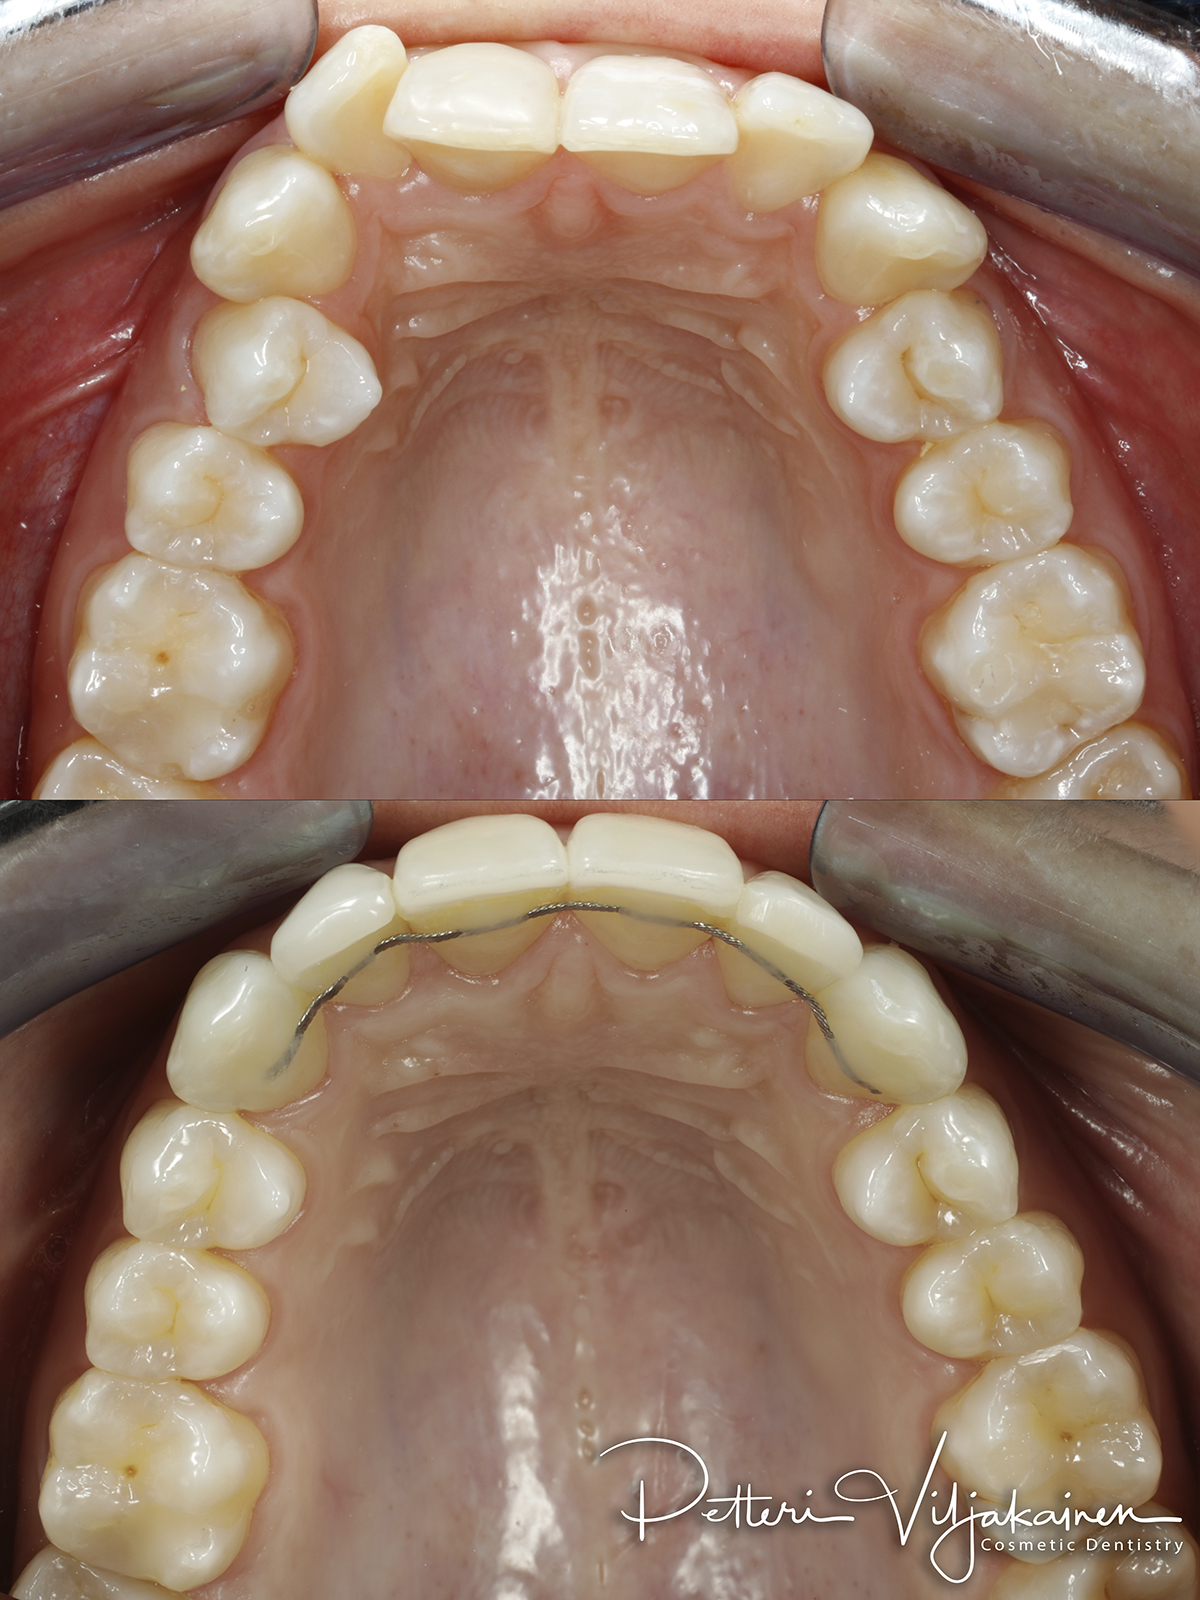

Retentio

Oikominen on aina retention eli lopputuloksen pysyvyyden kanssa koko loppuelämän hoito. Halusit tai et. Oikomisen jälkeen hampaat pyrkivät palautumaan takaisin kohti lähtötilannetta. Palautuminen on voimakkainta ensimmäisen vuoden aikana. Kaikkien oikomishoitojen jälkeen hampaat pitää "lukita" uusille paikoilleen hoitomenetelmästä tai iästä riippumatta. Valitettavan monelle potilaistani oikomista on tehty jo lapsuudessa, mutta koska lopputulosta ei lukittu aikoinaan mitenkään, esimerkiksi retentiolangoilla, palautuvat hampaat iän mukana jonkin verran tai pahimmassa tapauksessa kokonaan takaisin lähtöpisteeseen. Hampaisto ahtautuu luonnollisesti jonkin verran myös iästä johtuen.

Vaihtoehtoja retentioksi on kaksi: Joko hampaiden taakse pistetään kiinni ohut muotoon taivutettu metallilanka eli retentiolanka, tai öisin pidetään ohutta retentiokalvoa. Retentio valitaan sen perusteella kuinka paljon ja mihin suuntaan hampaita on liikutettu. Paras takuu on valiota molemmat jos purennassa on retentiolangalle tilaa.

Normaali käytäntö retentiolle on että alahampaiden taakse tuleee retentiolanka. Tämän lisäksi sekä ylä- että alahampaisiin tilataan lisäksi retentiokalvot eli Viverat. Ylähampaiden takana on purennassa niukalti tilaa eli sinne retentiolankaa ei aina saa mahtumaan.

Alla eri tyyppisiä retentiolankoja: